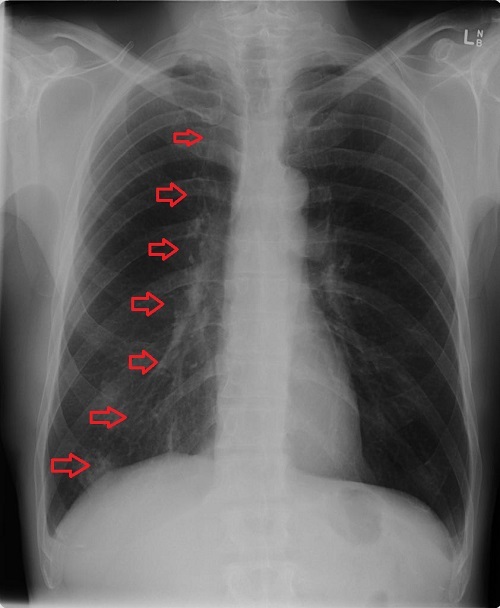

Pneumotórax

Insuficiência respiratória

Pneumonias recorrentes